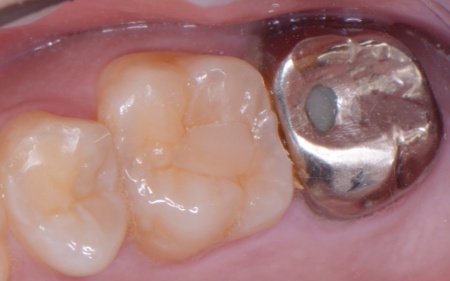

拝見したところ、左下奥歯(第1大臼歯)は以前、歯根分割処置が行われていました。

歯根分割処置とは、歯周病や虫歯などにより複数ある歯根のうちひとつだけがダメージを受けた場合に施す外科的な治療法です。

特に根が複数ある大臼歯に対して行われ、問題のある歯根のみを分割して抜くため残りの健康な歯根を残すことが可能です。

しかし残していた歯根の状態も悪化しており、治療しても温存は困難と判断しました。

また、右の上下奥歯2本に装着されている白い被せ物や銀歯が劣化により歯に合わなくなり、虫歯の再発リスクが高まっていました。

左下奥歯はこのまま放置すると細菌感染を引き起こすため抜歯が必要なこと、抜歯後に歯を補うため人工歯根を利用したインプラント治療を提案し、同意いただきました。

③矯正治療と並行して左下奥歯を抜歯し、インプラント治療を行う。

インプラントを支えるための骨の量が十分でないため、人工材料を用いて骨を再生させる骨造成(GBR)を併用しながらインプラントを埋入する。